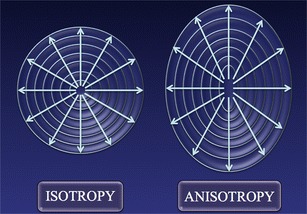

The most important anatomical factor, however, is anisotropy, which reflects the direction dependence of certain properties that some organs demonstrate (Fig. 8). Most of the current knowledge about the effects of anisotropy on the transmission of shear waves derives from an experimental work by Gennisson on an animal model using supersonic shear waves imaging [9], a variant of the ARFI technique in which the pulses generating the shear waves move more quickly in tissues.

Fig. 8.

Schematic representation of an isotropic and an anisotropic object: in the latter, properties vary in the different planes. The term comes from ancient Greek words “ἄνισoς” and “τρoπή”